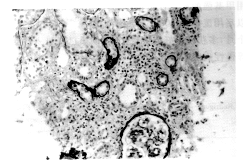

3.病理改变特点:以间质水肿、炎性细胞浸润和肾小管变性萎缩为突出表现,浸润的炎性细胞为单核及淋巴细胞。肾小球正常或轻度系膜细胞及基质增生,1例肾小球基底膜呈缺血性皱缩,3例有轻度系膜增生,肾血管均未见异常。3例有不同程度的间质纤维化,免疫荧光检查,肾小球及肾小管基底膜未见免疫复合物沉着(图1)

图1 治疗前可见间质弥漫性炎症细胞浸润

及间质水肿HE染色×200